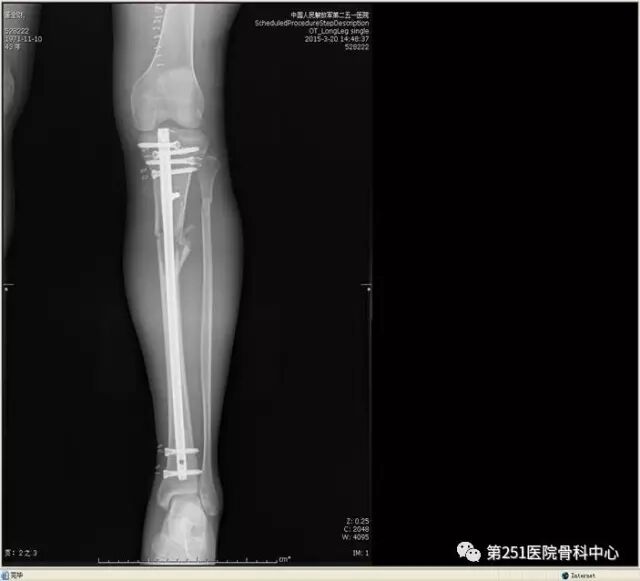

病例1:男性,40岁,车祸伤,胫腓骨多段骨折。

![]()